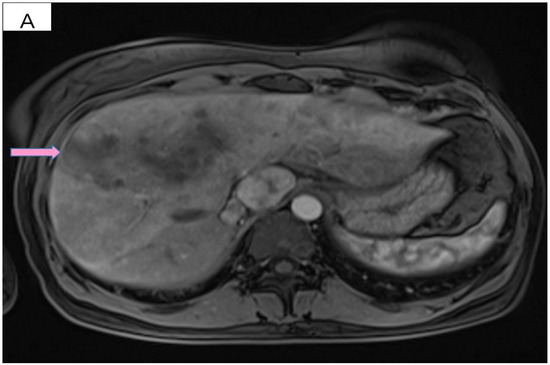

The physical exam revealed a tumor in the outer quadrants of her left breast measuring 3/2.5 cm which was associated with erythema, skin thickening, purulent mammary secretions and a mobile ipsilateral axillary adenopathy. Magnetic resonance imaging (MRI) revealed a lower outer quadrant tumor with extensions to the upper outer quadrant (Figure 1A,B). The biopsy and the following pathology exam of this ill-defined mass showed an invasive mammary carcinoma of no special type, moderately differentiated (grade 2 of 3) with solid areas of in situ carcinoma of mixed differentiation and extensive comedonecrosis (Figure 2). Further immunohistochemistry showed that the tumor expressed estrogen receptor (ER 70%), progesterone receptor (PR 20%), HER2 overexpression and a Ki-67 index of 40% (luminal subtype, HER2+). An ulterior whole-body computed tomography (CT) highlighted a suspicious 44/40/52 mm tumor in the caudate lobe of the liver and no other metastases. For a better description of the lesion, an MRI was ordered which described it as a focal hyperplasic nodule (HFN). Lab reports and tumor-marker carbohydrate antigen 15-3 were within normal values (CA15-3 = 18.8 U/mL). Correlated with these findings, the tumor was staged as T4bN1M0 stage IIIB according to the AJCC cancer-staging manual (eighth edition).

Figure 1.

(A) T2 weighted MRI of left breast demonstrating skin thickening (3.2 mm) associated with hypersignal suggestive of edema. (B) T1 weighted MRI showing the regional contrast sample located in the lower outer quadrant extending to the upper outer quadrant (marked by arrows).